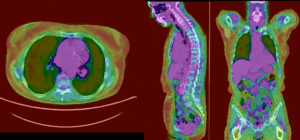

this is the fixed PET/CT image. All images are aligned into this space lleft this is the moving image. The transform is calculated by matching this to the reference image

fixed image/target moving image

PET overlay ; BSpline registration of full volumes. 9 x 9 x 5 gridPET overlay ; BSpline registration of full volumes. 9 x 9 x 5 grid

PET overlay ; BSpline registration of full volumes. 11 x 11 x 7 gridPET overlay ; BSpline registration of full volumes. 11 x 11 x 7 grid